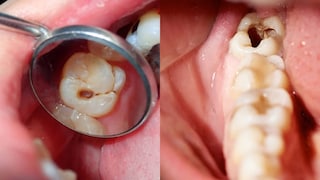

বছরে দুবার দাঁতের পরীক্ষা করান – এটি একটি অত্যন্ত গুরুত্বপূর্ণ কিন্তু প্রায়শই উপেক্ষিত পরামর্শ। এমনকি যদি আপনার কোনও সমস্যা নাও হয়, তবুও বছরে কমপক্ষে দুবার দাঁতের ডাক্তারের সাথে দেখা করতে ভুলবেন না। কখনও কখনও, দাঁত বা মাড়ির সমস্যা প্রাথমিক পর্যায়ে ব্যথার কারণ হয় না, তবে অভ্যন্তরীণভাবে বৃদ্ধি পেতে থাকে। সময়মত চেকআপ গহ্বর, মাড়ির প্রদাহ, পাইওরিয়া বা অন্যান্য সংক্রমণ প্রাথমিক পর্যায়ে সনাক্ত করতে সাহায্য করতে পারে, যার ফলে চিকিৎসা সহজ হয়। পেশাদার পরিষ্কারের মাধ্যমে টার্টারও দূর করা হয় যা নিয়মিত ব্রাশ দিয়ে অপসারণ করা যায় না।